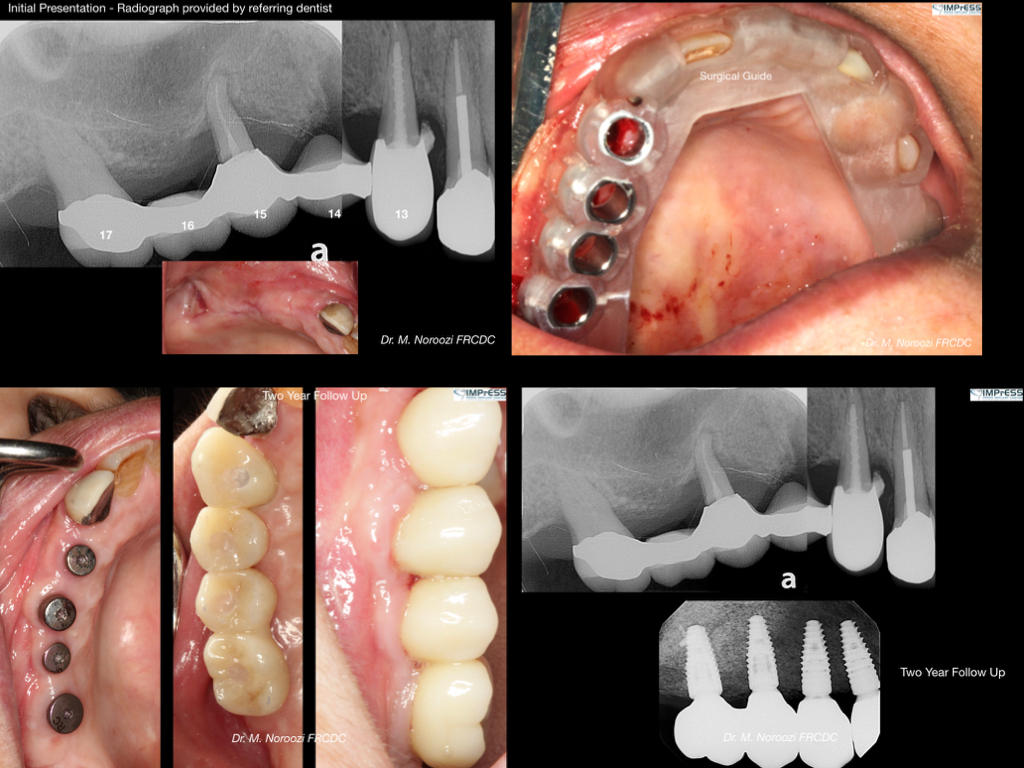

CBCT Guided Implant Surgery – Restoratively Driven Implants

Multiple Dental Implants IMPrESS Perio Implant Center Burnaby Implant Specialist Vancouver Implant Center Dr. Mehdi Noroozi Implant Specialist in BC